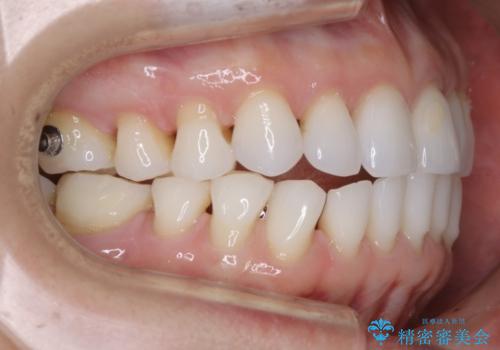

【非抜歯】マウスピースでオープンバイトを治す

- 歯ぎしりや食いしばり、噛み合わせの治療とガタつきを治したいとのことでご来院されました。

検査の結果、前歯と臼歯の高さに差があり、前歯が全く当たらない状態になっているため歯ぎしりによって奥歯が削れてしまっているという状態でした。

マウスピースの矯正装置を用い、ガタつきを治しつつ奥歯を沈めていくことで噛み合わせ全体の改善を図りました。